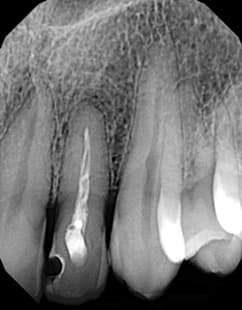

Digital X-ray–Everything I Didn’t Know I Wanted

During the journey through my 40-year career as a hygienist, I have cleaned a lot of teeth, talked to a lot of patients, and of course, taken a lot of X-rays. A lot of things have changed over the years, and one of the most important changes happened in radiography. I have used film from the beginning except for the last two years when the office switched to DEXIS®. Before then, my team members and I were generally satisfied with film, and we wondered why we needed digital. Now, we all say we would never want to practice without it—it’s that significant in our practice. When I first

By Wendy Briggs, RDH The incredible technological advancements in dentistry in recent years have enhanced our role as preventive therapists. One of the most significant changes has been the emergence of digital radiography. Digital radiography provides some very obvious benefits, yet can bring with it some costs. One of the most common mistakes I encounter when it comes to digital radiography, is a practice not having enough equipment to handle the demand for X-rays. Radiograph recommendations were updated by the ADA as recently as 2005. Yet many of us haven’t taken the time to step back and evaluate what we are doing and decide if our protocol should be